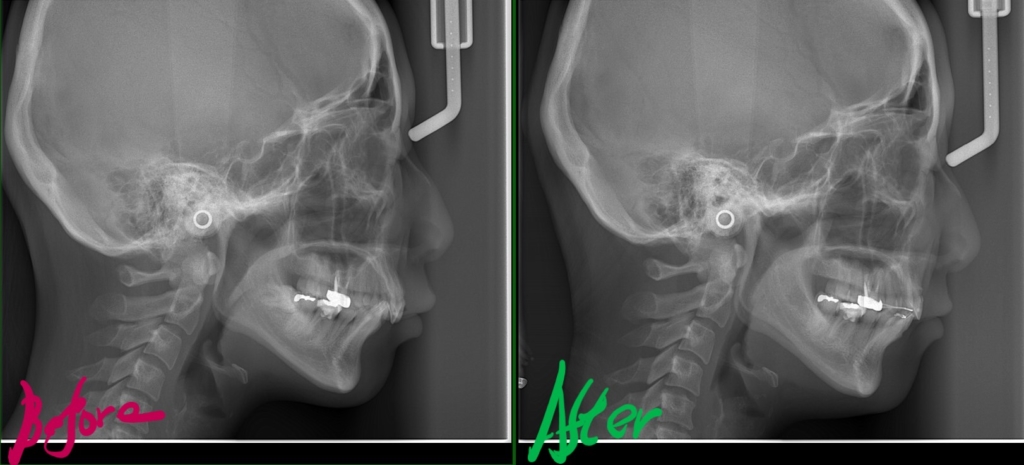

では、矯正治療前後の「レントゲン写真」や「笑顔、口元の写真」などを比較してみましょう。

まずはレントゲン写真の比較です。

左側が矯正治療前、右側が矯正治療後